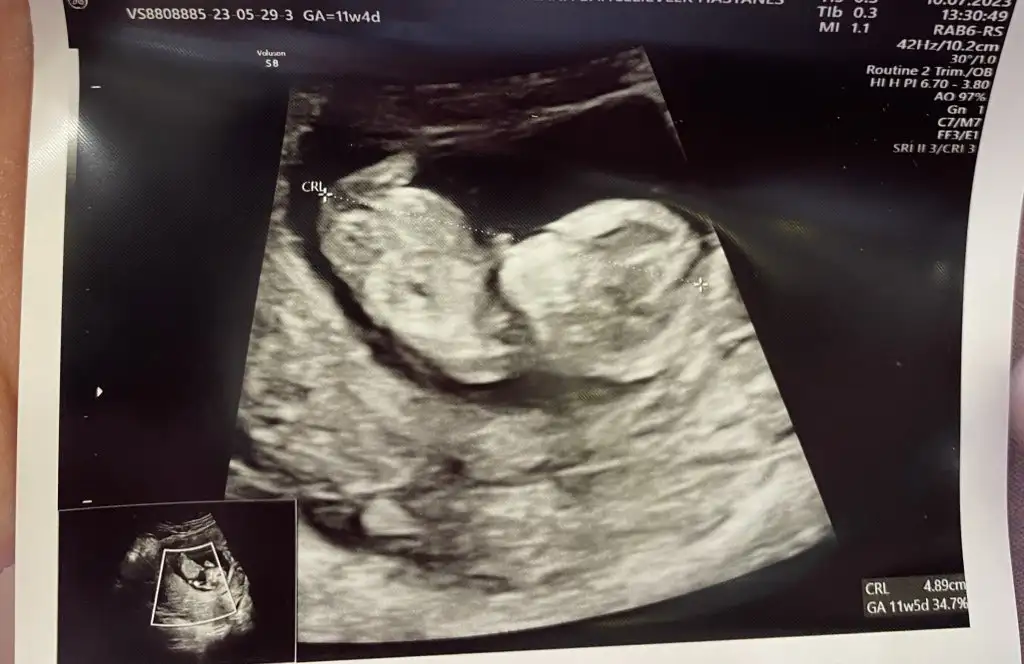

11 Haftalık olduk bizde kızlar tahminlerde değişen var mı bakabilir misiniz 🙋🏻‍♀️

Eklentiler

• IMG_5273.webp

IMG_5273.webp

35,9 KB · Görüntüleme: 61

• IMG_5272.webp

IMG_5272.webp

44,5 KB · Görüntüleme: 49

• IMG_5271.webp

IMG_5271.webp

45,8 KB · Görüntüleme: 72